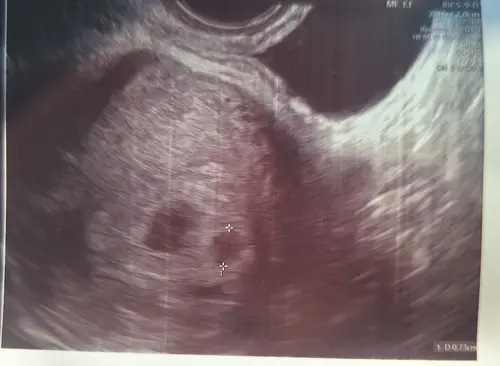

Ja hier 🙋🏼♀️ 5w5 dagen

Nee hoor, dat was mijn zwangerschap, inmiddels zijn de meiden bijna 8 maanden.

Ik vond de zwangerschap lichamelijk heel zwaar, ben op 12 weken al gestopt met werken. Uiteindelijk wel kunnen uitdragen tot 37 weken.